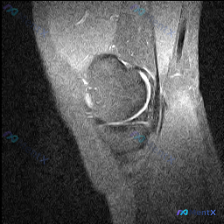

最近看到这份膝关节MRI读片请求,核心提示是软骨异常,整理了完整的资料和分析思路分享给大家: 基本影像信息 这份是膝关节矢状位MRI图像,属于T2加权/质子加权压脂序列,图像分辨率低、噪声大,仅能显示髌骨、股骨远端前部、胫骨近端前部和髌股关节局部区域,无法判断是内侧还是外侧层面。 影像具体发现 1....